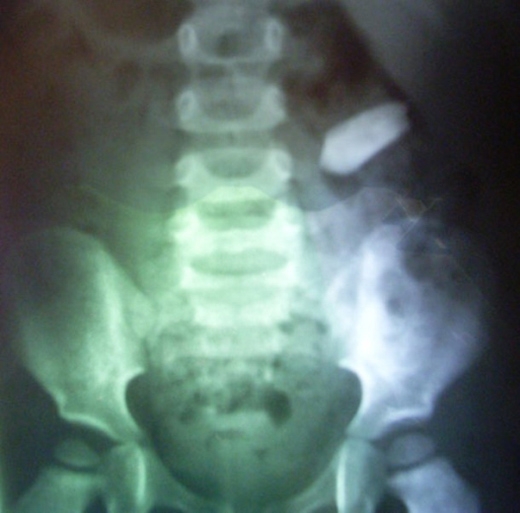

2. Viên đạn ghim vào cột sống